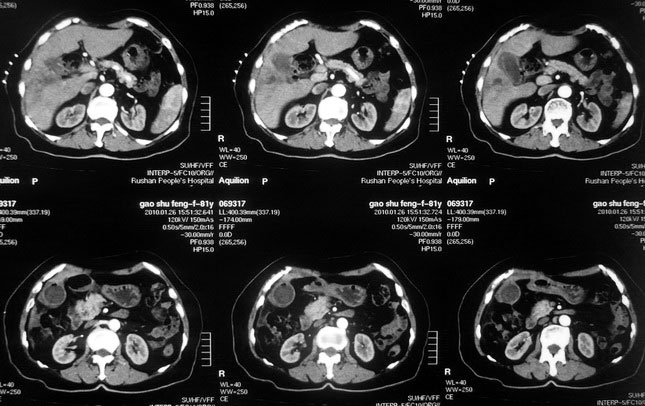

女,80岁既往有胆系手术史。近2月出现食欲不振,近20天出现畏寒发热,体重约下降10kg,体温一般在38℃左右。血常规wbc正常,中性比例88%,cea 10.3,afp、ca199均正常。做过一次肝穿,抽出约3ml仿佛脓性液体。这是她的增强ct扫描,请大家帮帮忙。另外想问问肝脓肿和胆管细胞癌的ct表现有什么区别。谢谢了。

【湘江一滴】化脓性胆囊炎及胆管炎,肝内胆管积气、积液、扩张;胆囊壁增厚、强化;胆周积液。未见肝内占位征象。

【shuiyuan】化脓性胆囊炎及胆管炎,肝内胆管积气、积液、扩张;胆囊壁增厚、强化;胆周积液.

肝脓肿动脉期呈明显环形强化或蜂窝状强化,胆管细胞癌动脉期强化不明显,且伴肝内胆管扩张。

【zenxisengming 】肝内胆管扩张积气,胆囊比环形增厚,胆囊周围渗出,未见占位性病变,应该是胆道化脓性感染

【sunbin】肝内见多个气体密度影伴气液面,胆囊壁增厚,胆囊周围低密度环绕,未见强化,支持化脓性胆管炎、胆囊炎。

最近复查ct,做了第二次穿刺抽脓,顺便做了涂片病理活检,结果找到恶性肿瘤细胞,诊断肝癌合并肝脓肿。看来大家都走眼了啊。